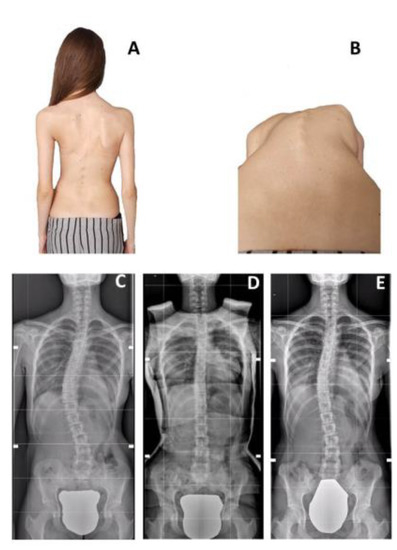

Does Risser Casting for Adolescent Idiopathic Scoliosis Still Have a Role in the Treatment of Curves Larger Than 40°? A Case Control Study with Bracing

La Maida, G.A.; Gallazzi, E.; Peroni, D.R.; Liccardi, A.; Della Valle, A.; Ferraro, M.; Cecconi, D.; Misaggi, B. Does Risser Casting for Adolescent Idiopathic Scoliosis Still Have a Role in the Treatment of Curves Larger Than 40°? A Case Control Study with Bracing. Children 2022, 9, 760. https://doi.org/10.3390/children9050760